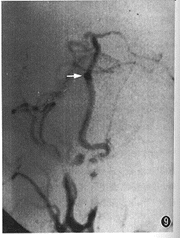

例2 男,38岁。复视,右眼视力下降半年。外院诊断颅咽管瘤,来本中心求治。体检:右外展神经麻痹,右眼视力0.8。CT平扫(图3):鞍旁4.0 cm×3.0 cm×5.0 cm高密度占位,右侧裂内1.0 cm×0.8 cm×1.0 cm高密度占位,边界清,周边呈蛋壳样钙化。MRI示鞍区、鞍上混杂信号占位,边界清,内有流空信号和不同强度短T1、长T2信号,周围脑组织受压水肿(图4,5)。MRA示右颈内动脉蛇形血管通道,累及右大脑中和大脑前动脉(图6)。DSA示右颈内动脉自岩段起呈蛇形迂曲扩张, 累及右M1、A1段及右后交通动脉,血管通道内血流缓慢,静脉窦期仍见对比剂滞留(图7,8)。右颈内动脉球囊闭塞加强试验阴性,但交叉代偿循环充盈试验阳性,先行右颞浅动脉-大脑中动脉搭桥术,术后24 h内,右颈外动脉造影显示吻合口通畅,遂行载瘤动脉近端球囊闭塞术,载瘤动脉闭塞后右颈外动脉造影显示通过吻合口的血流增加(图9)。术后1年随访,症状、体征消失,生活工作正常,CT复查:瘤周脑组织水肿消失,大小无明显变化。

图9 右颈外动脉造影,显示右颞浅动脉-大脑中动脉吻合口通畅,箭头示吻合的位置